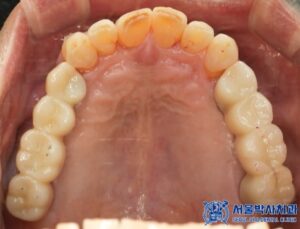

발치를 진행한 후, 우선적으로 하악 좌우 어금니

부위부터 무절개 임플란트를 총 4개 심었습니다.

이 과정에서는 뼈 이식도 병행하였습니다.

이후 상악 좌우도 순차적으로 치료를 진행하였으며,

상악 좌우는 모두 뼈이식을 동반한

무절개임플란트를 총 6개 식립하였습니다.

임플란트 수술이 끝나고 임플란트가 잘 고정된 후에는,

저희 서울박사치과 원내기공소에서 제작한

개인 맞춤형 보철물을 세팅해드렸습니다.

치료 마무리 후 사진입니다.